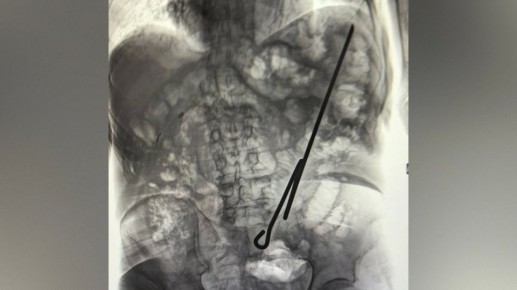

Специалисты

хирургического отделения Воронежской городской клинической больницы №3 (ВГКБ №3) рассказали самые запоминающиеся

случаи ночного дежурства 28 января. В ту ночь врачи извлекли из тел пациентов паразита и самодельный инструмент....